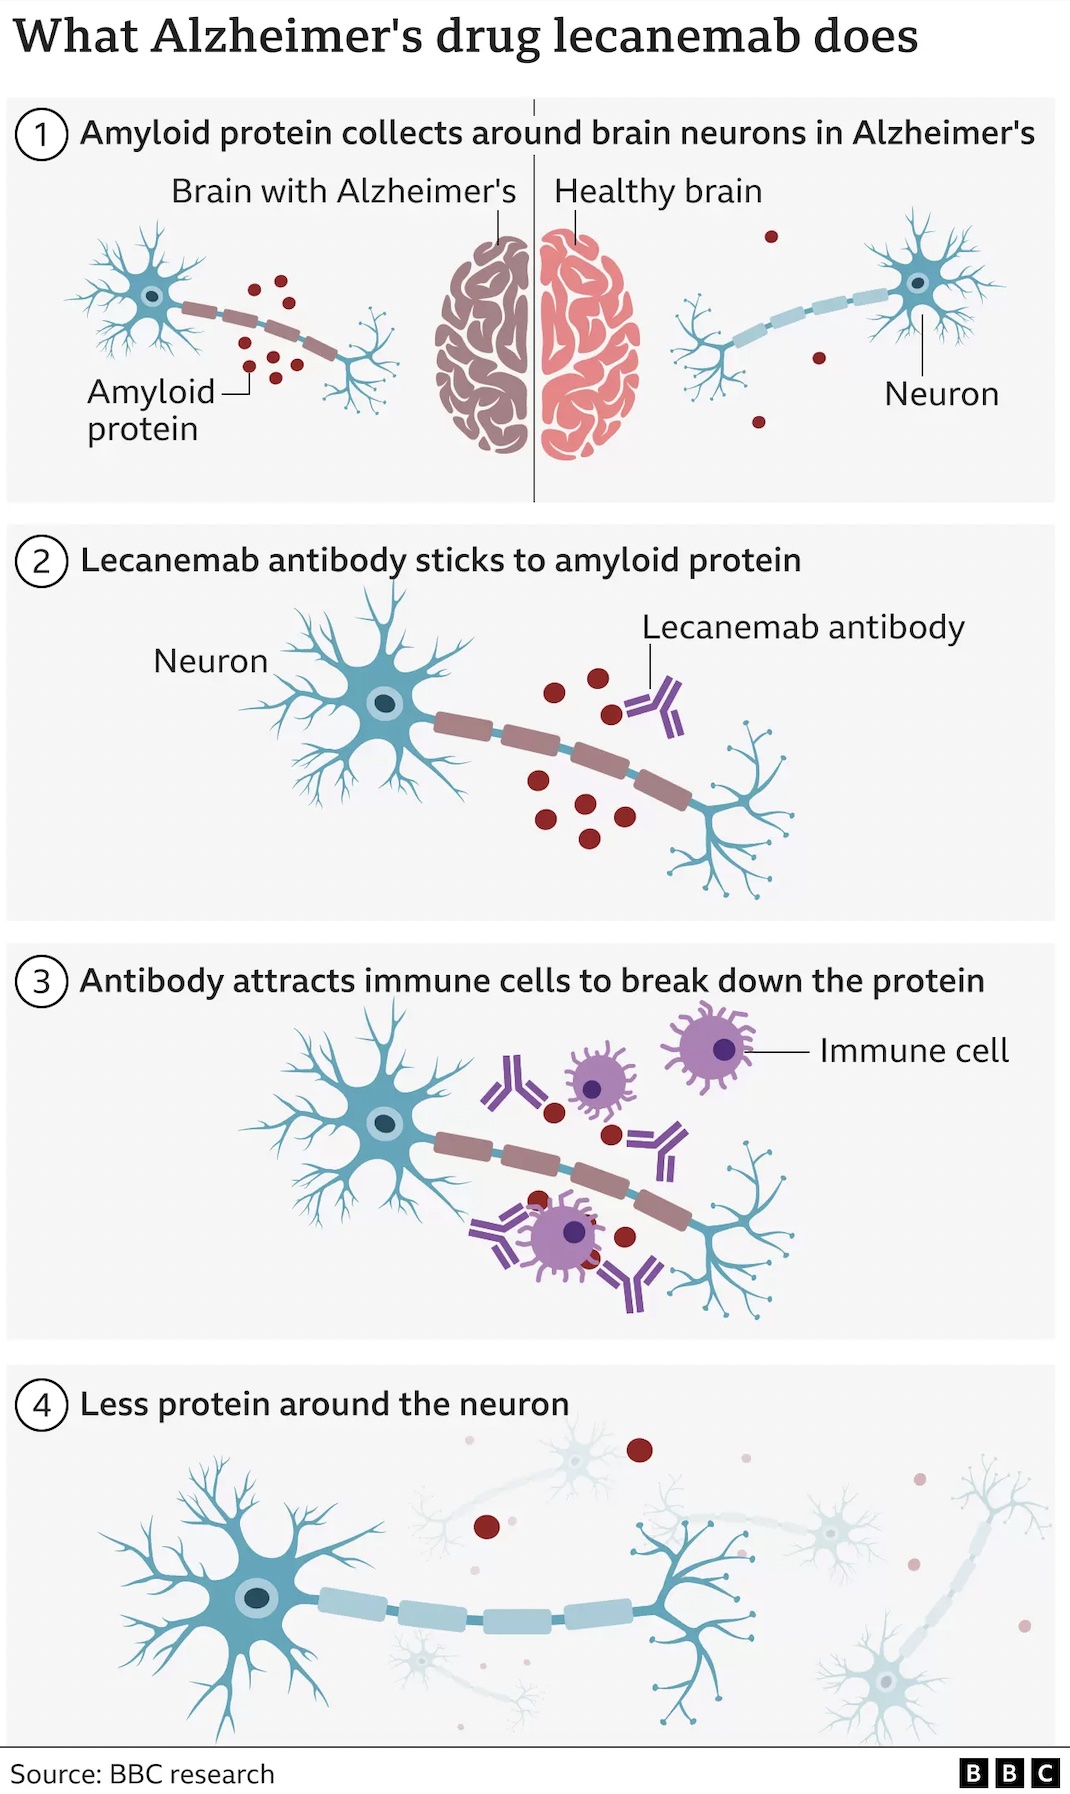

Lecanemab is designed to attack what is known as the ‘beta amyloid’, a substance that builds up in the brains of people with Alzheimer’s.

Amyloid is a protein that clumps together in the spaces between neurons in the brain and forms distinctive plaques that are one of the hallmarks of Alzheimer’s. Lecanemab is an antibody that has been engineered to tell the immune system to clear amyloid from the brain.